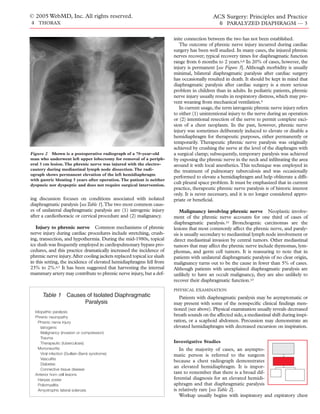

Figure 2 Shown is a postoperative radiograph of a 70-year-old            a surgical clamp; subsequently, temporary paralysis was achieved

man who underwent left upper lobectomy for removal of a periph-          by exposing the phrenic nerve in the neck and infiltrating the area

eral 3 cm lesion. The phrenic nerve was injured with the electro-        around it with local anesthetics. This technique was employed in

cautery during mediastinal lymph node dissection. The radi-              the treatment of pulmonary tuberculosis and was occasionally

ograph shows permanent elevation of the left hemidiaphragm

performed to elevate a hemidiaphragm and help obliterate a diffi-

with gastric bloating 3 years after operation. The patient is neither

dyspneic nor dyspeptic and does not require surgical intervention.